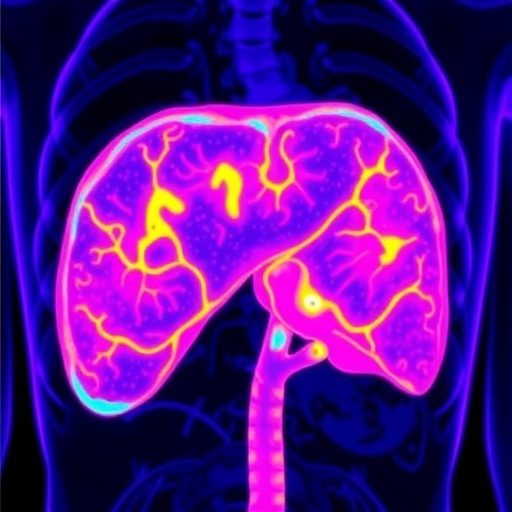

In the realm of surgical oncology, precise tumor delineation is paramount for successful intervention, especially during liver surgeries where the distinction between healthy and cancerous tissue can be particularly intricate. Current imaging techniques often fall short in terms of providing real-time, reliable guidance. A recent study presents an innovative approach, leveraging the unique properties of endogenous substances found within human liver tissues. This exciting advancement uncovers the utilization of intense autofluorescence in the second near-infrared window (NIR-II, 1,000–1,700 nm), facilitating a breakthrough in visualizing liver malignancies during surgical procedures.

The identification of these autofluorescent substances sets the stage for the development of a novel imaging technique known as tissue autofluorescence NIR-II imaging (TANI). Unlike conventional imaging modalities, TANI operates without the need for exogenous contrast agents, thus promising to enhance the safety and efficiency of liver surgeries. This non-invasive method harnesses the inherent optical properties of tissues, providing surgeons with a powerful tool to improve intraoperative decision-making and outcomes.

Testing the capabilities of TANI revealed extraordinary contrast ratios, averaging at an impressive 7.69 ± 0.52. This remarkable contrast underscores TANI’s potential to effectively distinguish between various types of liver tumors, including hepatocellular carcinoma, intrahepatic cholangiocarcinoma, and metastatic lesions, regardless of the patient’s underlying liver condition, be it cirrhotic or non-cirrhotic. The high sensitivity of the imaging method, pegged at 97.8%, and an equally striking specificity rate of 98.4% showcase TANI’s robust performance in real clinical scenarios.

In contrast to existing techniques that utilize fluorescence-guided surgery in the visible light spectrum or the first near-infrared window, TANI demonstrates a superior ability to delineate cancerous tissues with minimal interference from benign lesions, blood, or bile contaminants. This is particularly noteworthy as the presence of such contaminants often complicates surgical procedures and leads to diagnostic challenges. The findings suggest a paradigm shift in how surgeons will approach liver surgeries, providing them with critical information that could alter the course of treatment on the spot.